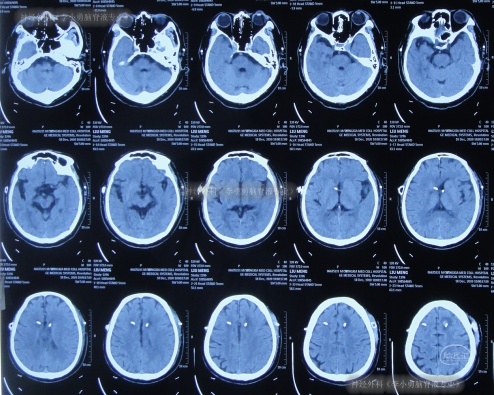

住院1周左右时间,期间曾3次查头颅CT(图-2)示脑室稍有扩张,但头晕症状慢慢消失,行走不稳缓解,认为“病情变好”出院。

图-2:3次查头颅CT